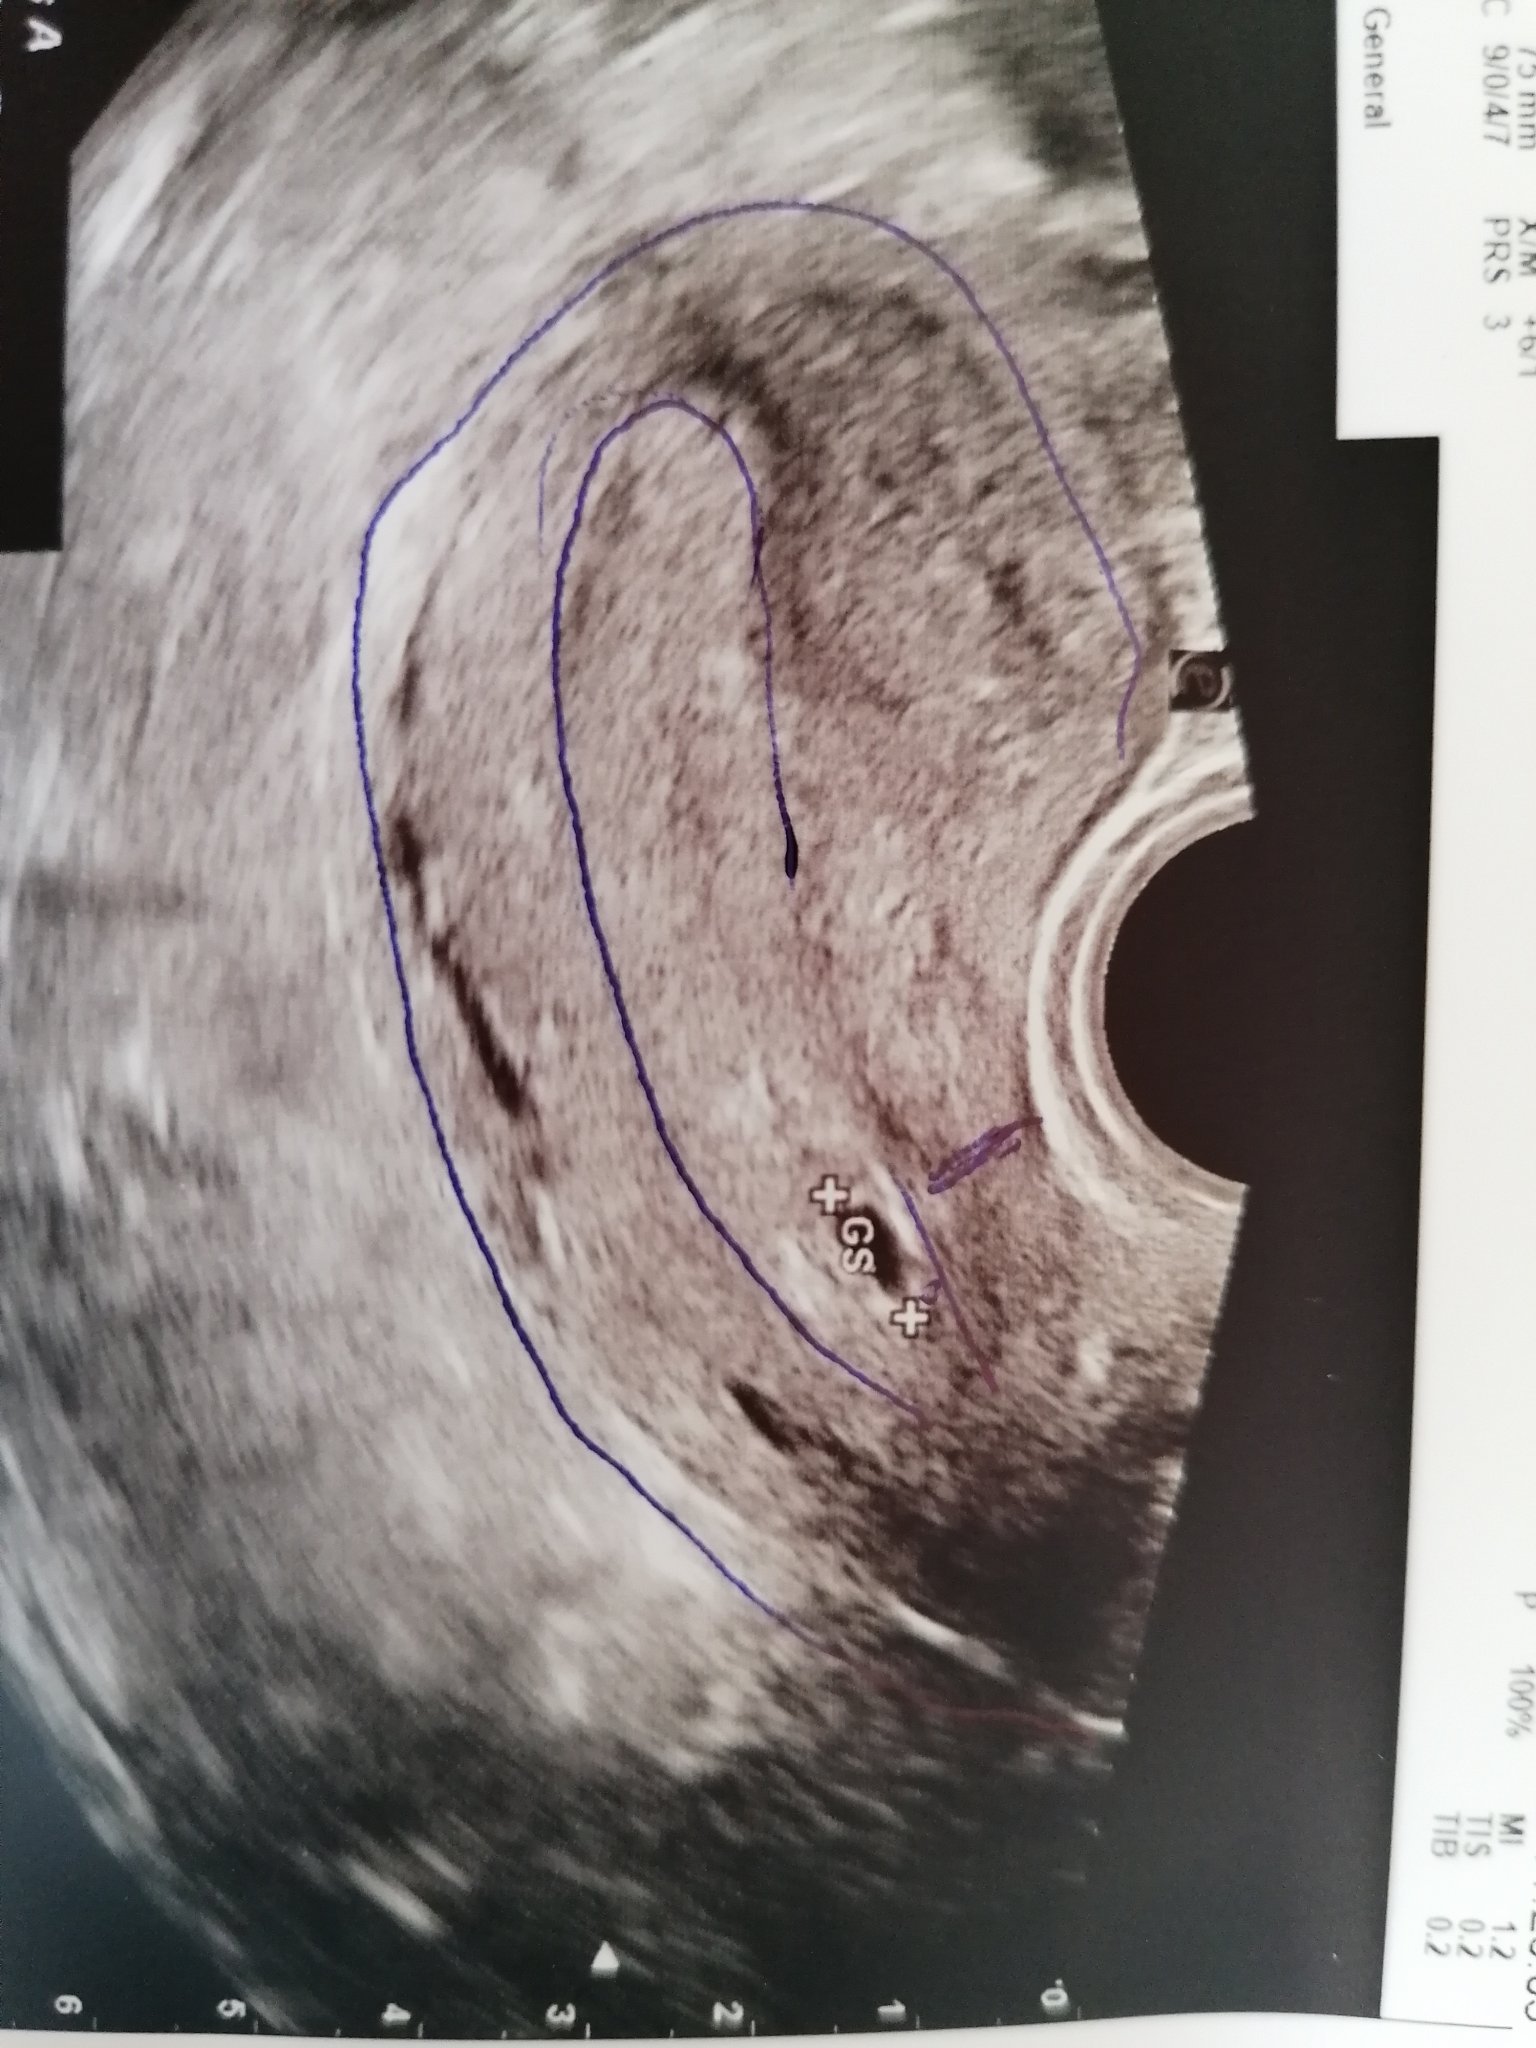

Здравейте бъдещи и настоящи майчета. Имам един въпрос,аз съм от юнските мами, но може и по рано ако съм със секцио да се роди. Това ми е трета бременност, първата завърши неуспешно и малкоя почина, втората родих близнаци и сега забременях, но преди малко ходих на АГ и ме наплаши. Трябвало да го махна, защоти съм го носела ниско, точно в началото щ, ще приложа и снимка.Пия дуфастон 3 х 1 и но шпа. Моля Ви дайде мнение какво да правя, каза ми и че ако започнела плацентата да се развива там била рискова бременност.....